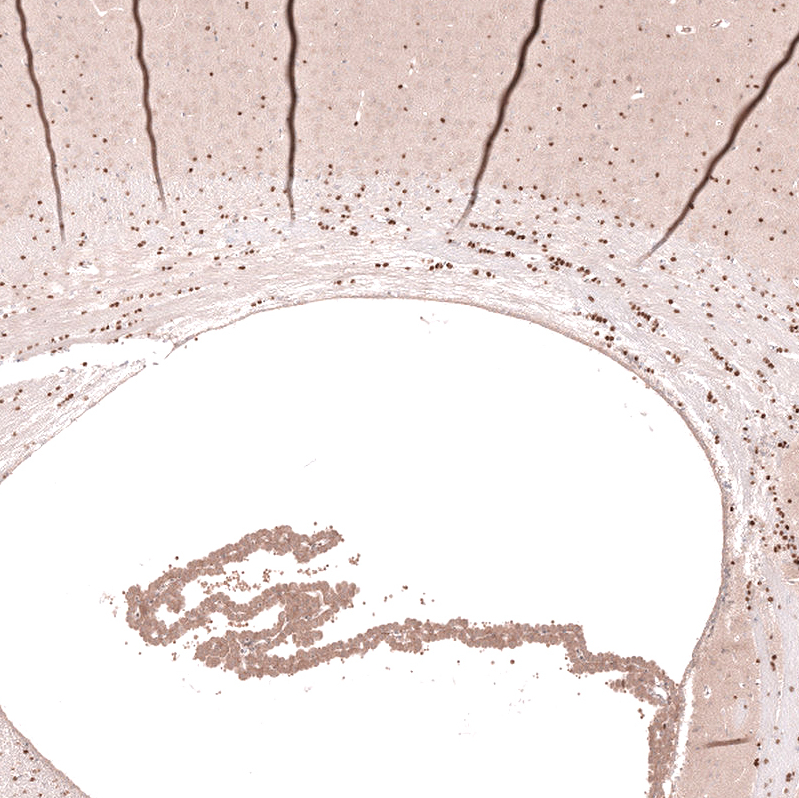

Immunohistochemical staining of human cerebral cortex shows strong nuclear positivity in oligodendrocytes.